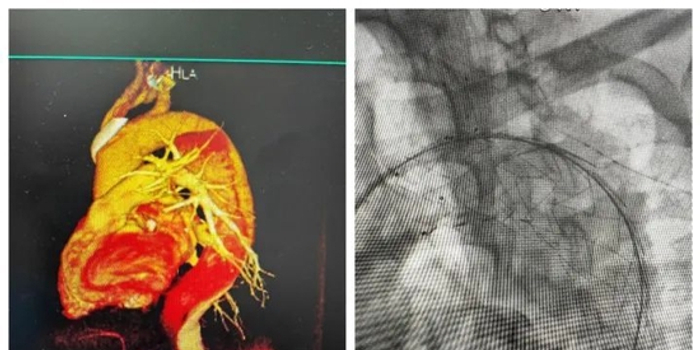

由于患者同时合并新发脑梗死,手术风险大,技术难度高,我院专家们术前进行了多次认真讨论,设计出最佳手术方案,并制定了详细的术前、术中、术后风险情况应急预案。今日中午,在国际医学中心李滨教授和西安交大一附院刘亚民教授共同指导下,张誉洋院长带领心血管内科四病区介入团队历时2个小时的精准操作,成功实施了我院首例胸-腹主动脉夹层动脉瘤覆膜支架腔内隔绝术。术中造影清晰显示患者内膜破口,通过股动脉送入支架推送器,将主动脉覆膜支架精准置入破口位置,达到100%覆盖。术后造影显示支架位置良好,手术达到满意效果。